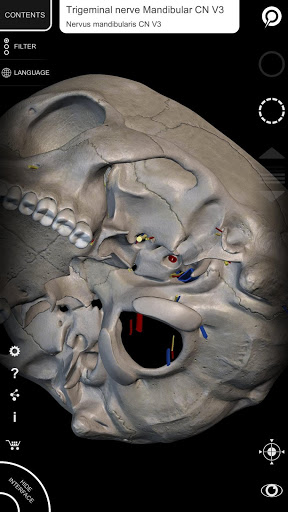

"Anatomy 3D Atlas" дозволяє легко та інтерактивно вивчати анатомію людини.

Завдяки простому та інтуїтивно зрозумілому інтерфейсу можна спостерігати кожну анатомічну структуру під будь-яким кутом.

Анатомічні 3D-моделі особливо деталізовані та мають текстури з роздільною здатністю до 4k.

Поділ за регіонами та попередньо визначені види полегшують спостереження та вивчення окремих частин або груп систем і зв’язків між різними органами.

• Нервова система

• Вибравши модель або шпильку, з’явиться відповідний анатомічний термін

• Анатомічні терміни та інтерфейс користувача доступні 11 мовами: латинською, англійською, французькою, німецькою, італійською, португальською, турецькою, російською, іспанською, китайською, японською та корейською

• Анатомічні терміни можуть відображатися двома мовами одночасно.